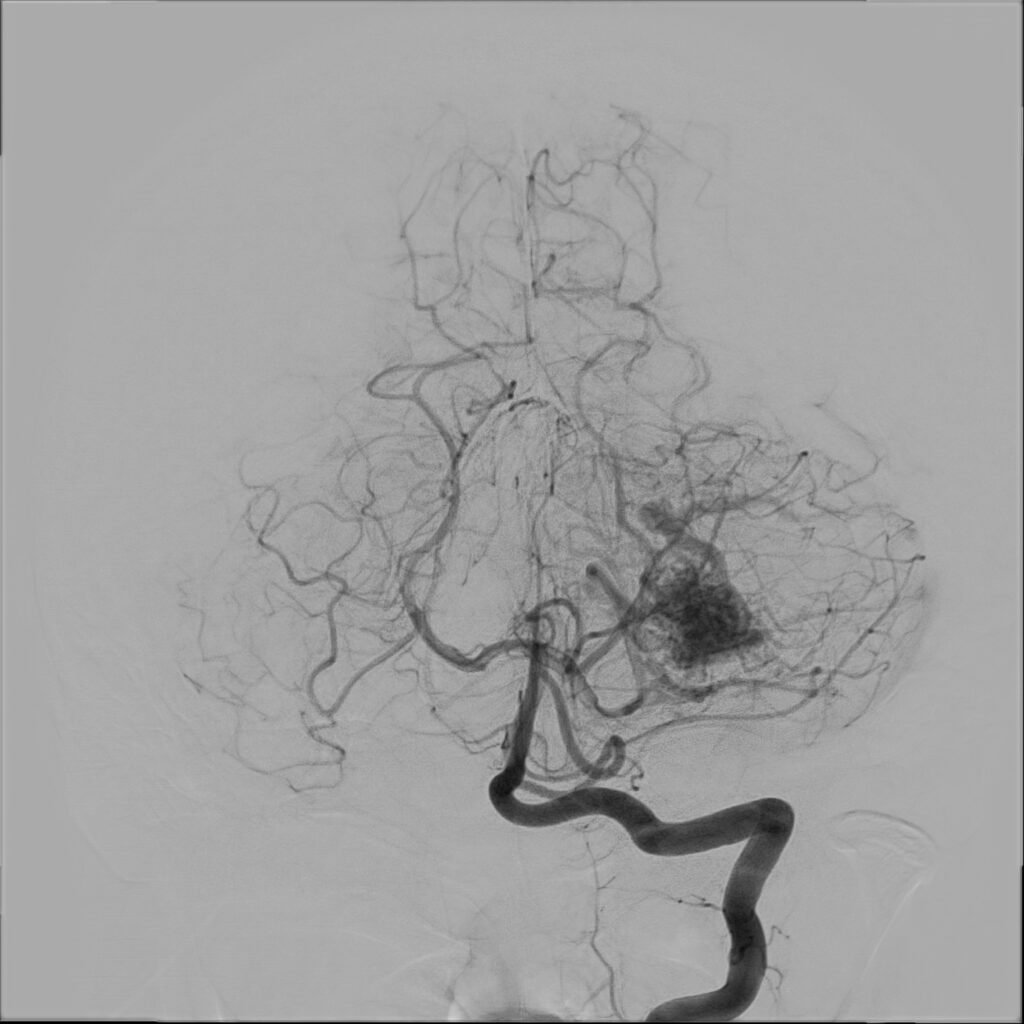

W przypadku prezentowanej pacjentki nie stwierdzono objawów neurologicznych poza bólem głowy. Po wstępnej diagnostyce została przekazana do Oddziału Neurochirurgicznego Szpitala Kopernika w Łodzi. W trybie pilnym wykonano angiografię cyfrową (DSA), która precyzyjnie uwidoczniła AVM.

Przeprowadzono embolizację części tętnic zaopatrujących AVM, co zmniejszyło ryzyko krwawienia śródoperacyjnego. Następnie wykonano kraniotomię podpotyliczną lewostronną z całkowitym usunięciem malformacji. Zabieg przebiegł bez powikłań, po zabiegu u pacjentki nie stwierdzono deficytów neurologicznych. Kontrolna angiografia potwierdziła całkowite usunięcie zmiany, co pozwala uznać pacjentkę za wyleczoną.